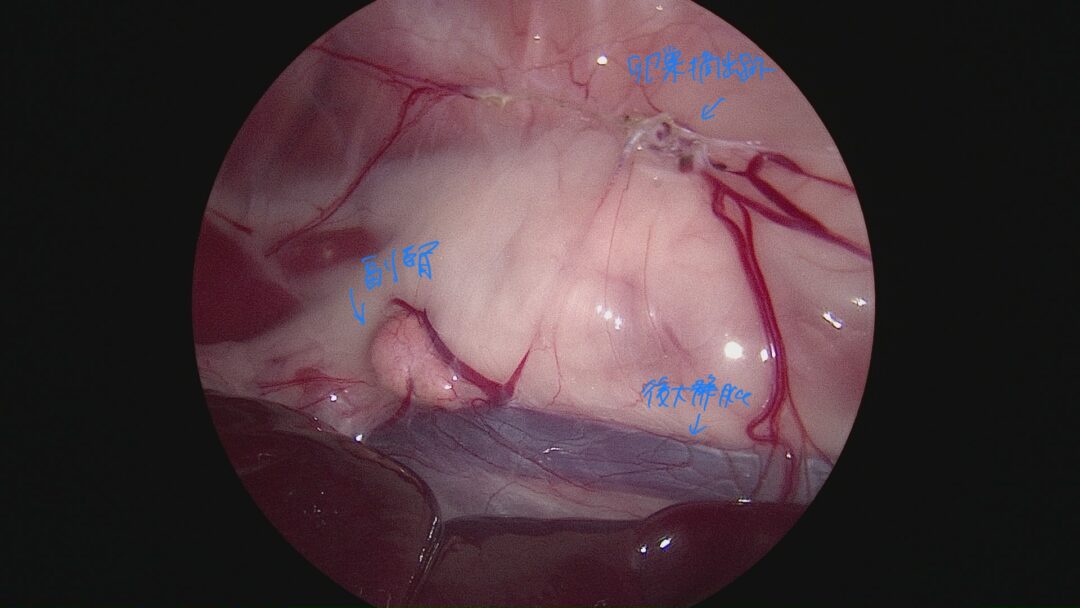

腎臓の無形成を確認するために後大静脈を副腎を露出しました。解剖学的に腎臓があると考えられる位置には腎臓は認められませんでした。